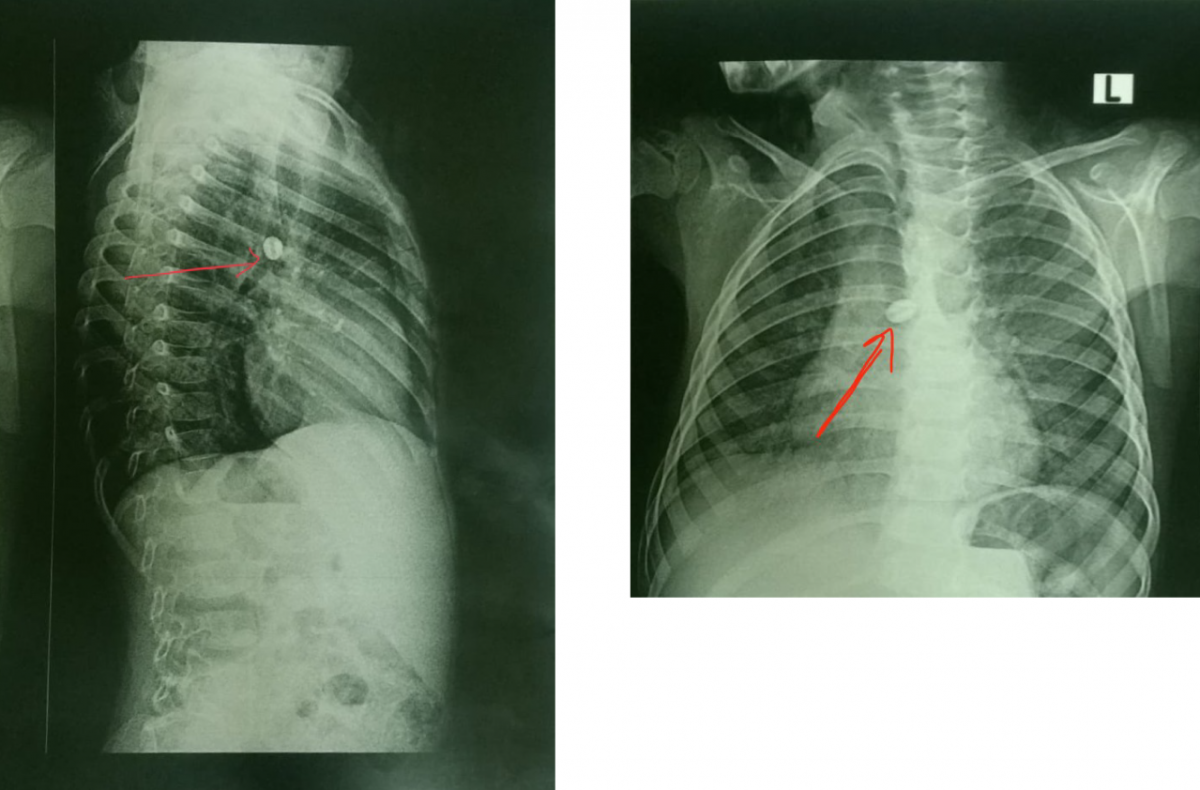

A 4-year-old boy came to the emergency department with stridor. He had a 19-hour history of foreign body inhalation of a rosary bead. The authors performed a rigid bronchoscopy. They used a crocodile forceps with one jaw inside the hole of the bead and the other jaw grasping the outer surface. Then they extracted the forceps and sheath at the same time.

Figure 1. Chest x-rays. The red arrow shows the location of the rosary bead.